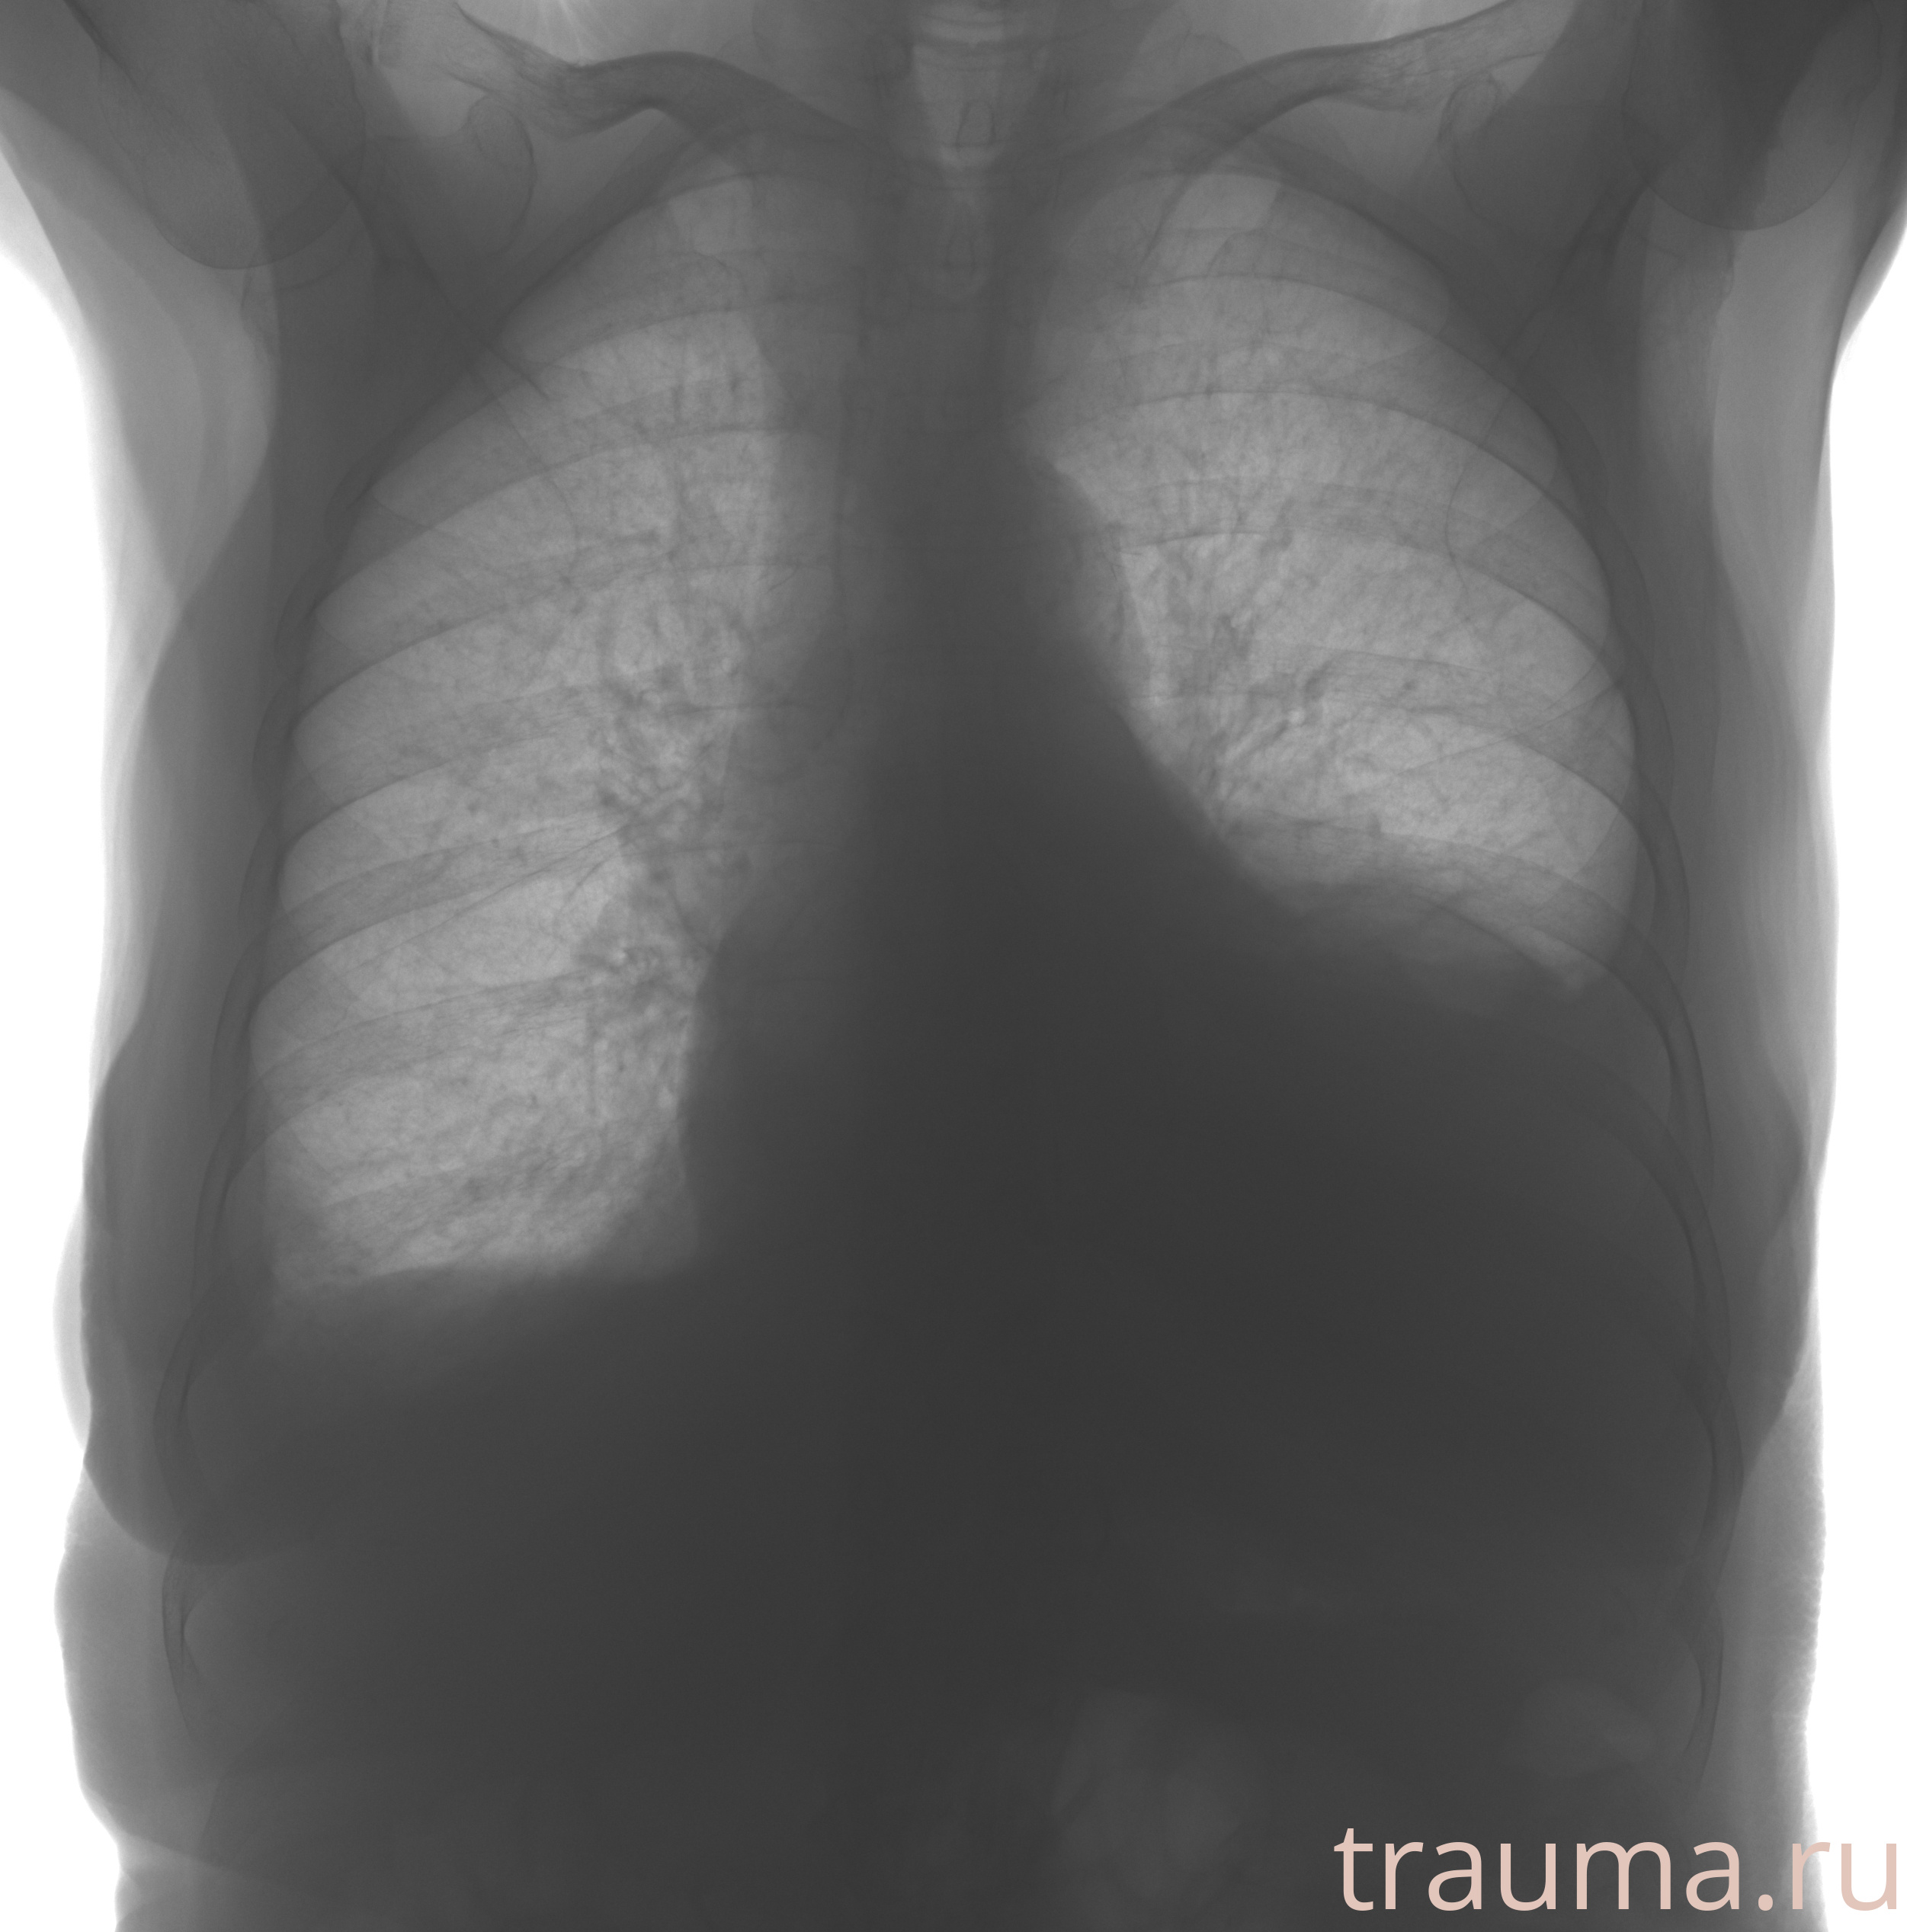

Рентген на дому: по вашему адресу приезжает врач-рентгенолог, травматолог-ортопед с мобильным рентгеновским аппаратом, проводит диагностику травмы или заболевания, делает необходимые рентгенограммы, дает рекомендации по дальнейшему лечению. Получить качественные снимки в домашних условиях возможно благодаря уникальной методике, разработанной МосРентген Центром для института  Склифосовского